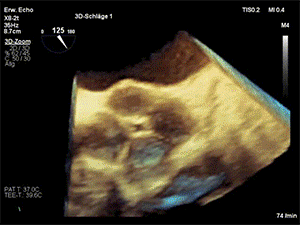

一名62岁女性患者因持续数月的呼吸困难就诊(NYHA心功能分级III级)。门诊经胸超声心动图发现中重度主动脉瓣反流后,进而接受经食管超声心动图检查。经食管超声心动图显示为极为罕见的四叶式主动脉瓣(图A,视频S1)。

(图A)三维经食管超声心动图

包含两个无冠瓣(N,non-coronary),瓣口面积保留,但存在中央对合间隙(图B;RA:右心房,LA:左心房,RV:右心室,LV:左心室,Ao.:升主动脉)。由此导致中重度主动脉瓣反流,相关参数包括:缩流颈宽度(VC)8 mm、压差减半时间(PHT)250 ms、有效反流口面积(EROA)0.28 cm²,且降主动脉可见舒张期血流反流。

(图B)双平面食管中段切面。缩写:N-无冠瓣,R-右冠瓣,L-左冠瓣,RA-右心房,LA-左心房,RV-右心室,LV-左心室,SVC-上腔静脉,Ao.-升主动脉。